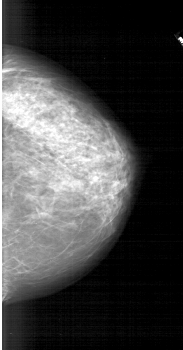

A_1744_1.LEFT_MLO

LEFT_MLO LINES 6721 PIXELS_PER_LINE 3376 BITS_PER_PIXEL 12 RESOLUTION 43.5 OVERLAY